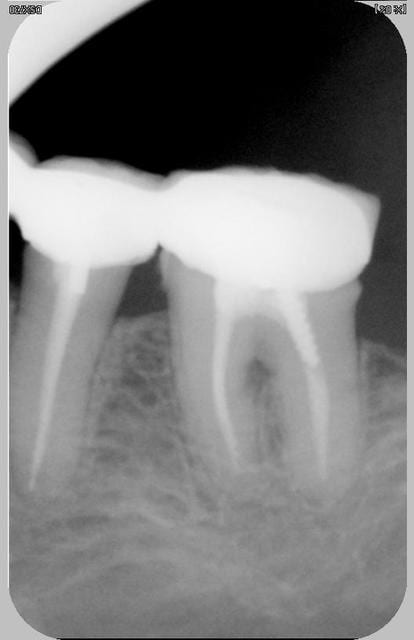

La série. Trois urgences différentes avec a priori un problème similaire.

Douleur à la pression localisée sur un dent particulièrement. Pas douleur au froid. Douleur au chaud et évidemment à la percussion.

Pas de gingivite autour de la dent si ce n'est ponctuellement en vestibulaire. La sonde pénétre nettement en interradiculaire unique siège de la douleur pour les 3 dents et uniquement en interradiculaire pour la radio 1 et 3.

J'ai désinfecté localement bain de bouche et ultrason. Je ne sais pas comment éliminer surement le problème (surtout pour 1 : bridge complet réalisé il y a un an sans problème jusqu'à maintenant)

venal pour la 1 il faut voir au niveau de la furcation,dernierement j'ai eu un cas proche de celui ci radiologiquement mais sur une mol sup et ça s"est exprimé par une fistule vest au bout de qq semaines d'interrogations j'ai alors hemisectionné(il s'agit d'une 26 amputation racine vest mes) et mis à jour une lesion granulomateuse interadiculaire ++